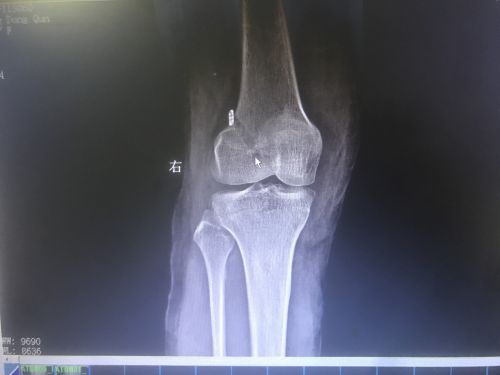

术后,前交叉韧带成功重建(鼠标所示)。

入院完善磁共振等检查,证实了之前的判断。由于韧带断裂无法自愈,只能通过手术修补。王靖主任医师组织医护人员商讨病情,制定周密的手术方案后,带领团队为患者施行关节镜下右膝前交叉韧带重建术。由于断裂的韧带失去修复功能,只得取大腿内侧韧带“移植”到受伤的右膝上;术中发现右膝半月板也有损伤,医生一并进行了缝合。手术历时2小时顺利完成,术后当天,唐女士就在医生指导下进行直腿抬高和扶拐行走训练,并于手术3天后出院。